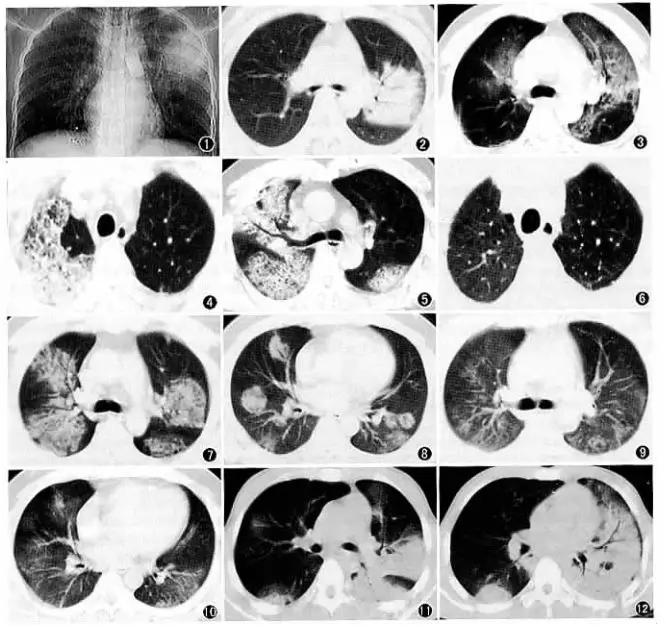

推测病毒感染后,机体出现了强免疫反应,巨噬细胞等免疫细胞吞噬病毒结合细胞(II型肺泡上皮细胞),造成严重肺损伤,这也与肺CT表现相符,感染一般为肺的外带、末梢、肺泡部位(图1。新冠病毒CT表现)。如果是RAS系统反射激活导致肺损伤,应该是肺的整体、多段损伤,而不是局部(图2.SARS肺炎CT表现)。

(图2.SARS肺炎CT表现,常侵犯多个肺段)

[2].图2来源:唐秉航.中华放射学杂志 2003.37(8):698-700.